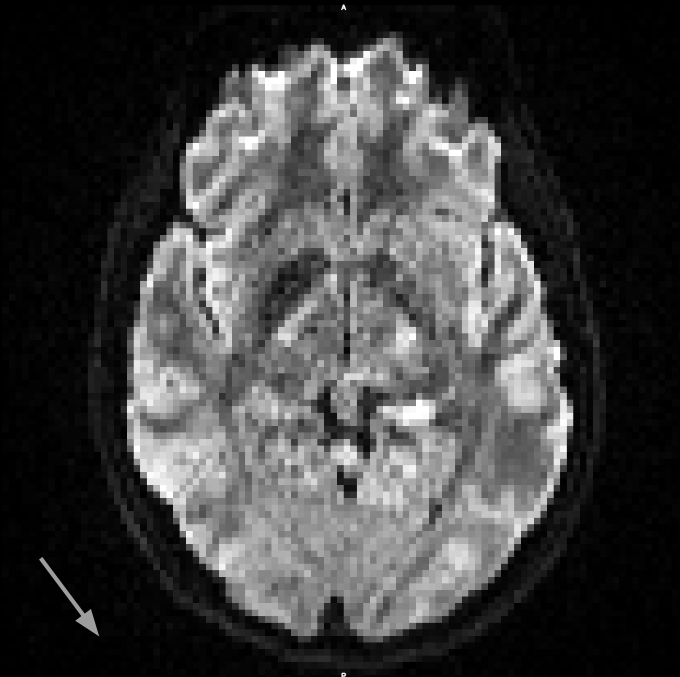

From these datasets, we use the five non-diffusion weighted () MRI scans each, as well as 30 diffusion weighted images (, diffusion gradient duration , spacing ). Each image consists of voxels with a resolution of . The data, and the effects of subject motion, are illustrated in Figure 6.

It can be seen in Figure 6 that subject motion during different phases of the acquisition leads to different types of artifacts. Results in Table 1 include the motion correction described in Section 3.3, which compensates spatial misalignments of different scans. However, motion can also lead to signal dropouts or to distortions within scans, which our current codec does not explicitly account for. This explains why q-space inpainting is less effective on the second as compared to the first scan. However, even on this challenging dataset that exhibits unusually strong artifacts, q-space inpainting still provides a benefit compared to all other alternatives.